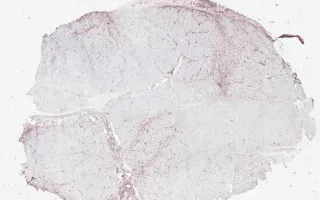

Muscle, Dermatomyositis, MHC stain

Immunohistochemistry for MHC show upregulation at the edge of the fascicles. C5b-9 staining is positive in many endomysial capillaries and myocytes, especially in perifascicular distribution.

This slide shows MHC stain. See related content for H&E and C5b-9 stains.